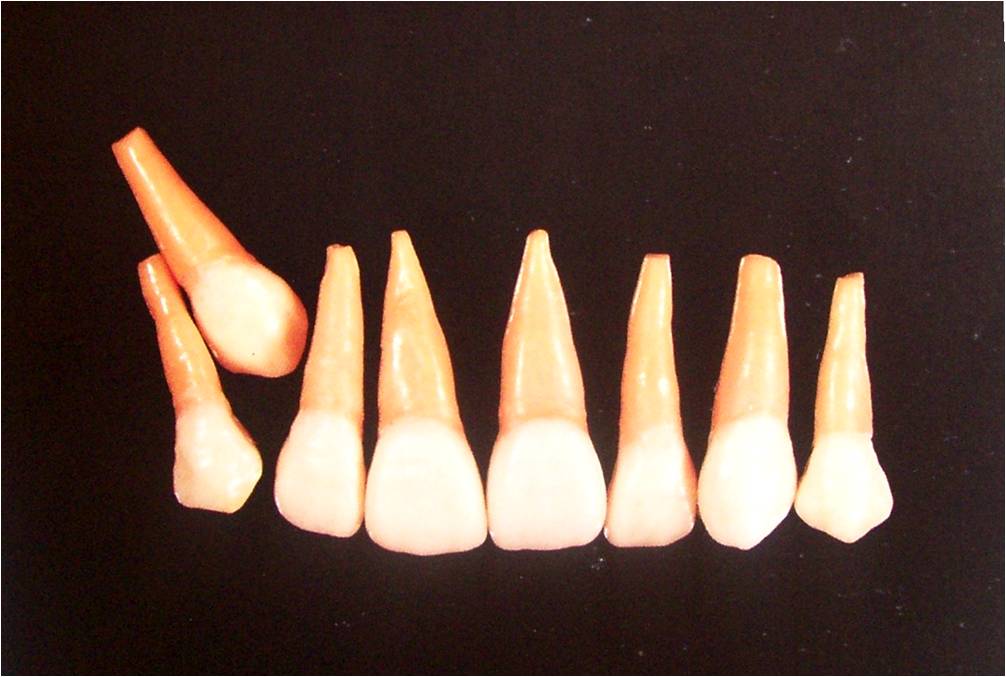

Indications for Canine Transplantation

Left : High labial ectopic position

Right : Close proximity to the apices of the adjacent teeth.

Transplantation of Labially Positioned Canine

Transplantation of maxillary canine with labial position.